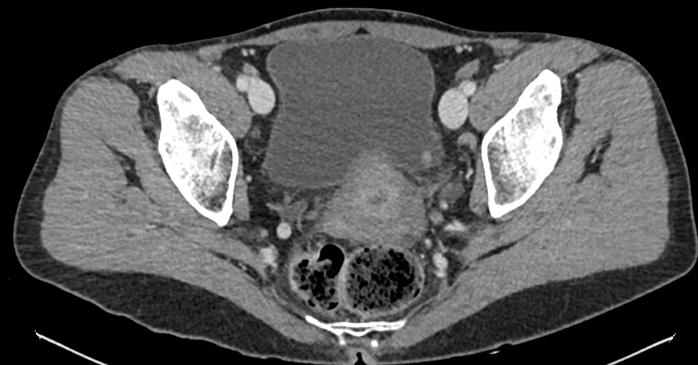

URO-TC solicitado para estudio diagnóstico inicial y por historia de cólico nefrítico sin evidencia de litiasis: Engrosamiento nodular en la pared postero-supero-lateral izquierda de la vejiga urinaria sospechoso de neoplásico de 8 x 5 mm. Ganglios subcentimétricos en región retroperitoneal, territorios ilíacos e inguinales bilaterales, destacando uno borderline (9-10 mm) periaórtico izquierdo, inespecíficos y a controlar evolutivamente.